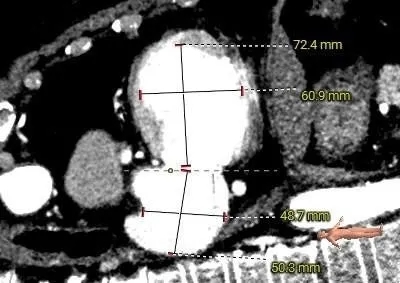

瓣架内径:25.0mm

瓣架外径:28.7mm

心室侧2mm:24.1mm

心室侧4mm:24.1mm

心室侧6mm:23.9mm

心室侧10mm:23.0mm

左房侧少量钙化

瓣架高度:约17.0mm

工作角度-瓣环切线位:RAO39°CRA38°

瓣下1.2mm处可见二尖瓣

LVOT:22.6mm,NEO-LVOT:23.5mm,模拟植入介入瓣后,流出道剩余面积尚可

预选瓣膜型号:ScienCrown TAVTF25mm,备TAVTF27mm瓣膜。

选瓣依据:该二尖瓣原置换生物瓣型号未知,CT测量生物瓣瓣环周长折算直径约25.0mm,瓣架高度约17mm。